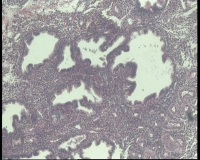

| 图片: | |

- 急!请老师看看34岁子宫内膜

| 性别 | 女 | 年龄 | 34岁 | 临床诊断 | 子宫内膜息肉? |

| 一般病史 | 末次月经:11月20日,近两个月无诱因性生活有阴道少许血性分泌物 | ||||

| 标本名称 | 宫内容物 | ||||

| 大体所见 | 膜样碎组织3.0厘米 | ||||